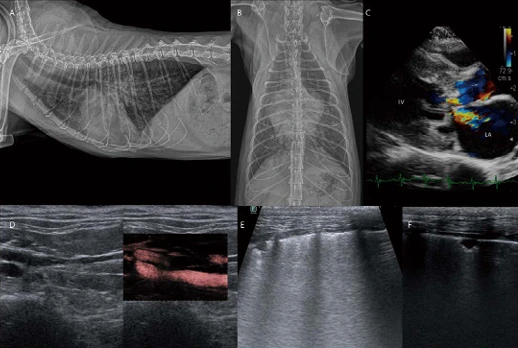

10살 중성화 수컷 Persian cat 3.76 kg 환자가 심한 기력 저하, 호흡 곤란 상태로 응급 내원하였습니다. 흉부방사선 검사에서 심비대, 흉수, 복수가 관찰됩니다(A, B). 심초음파 검사에서 LA, LV, RA, RV, left auricle, right auricle, CVC 모두 확장되어 관찰됩니다. 또한 LA, left auricle(atrial appendage), LV까지 심한 고에코성 smoke가 관찰됩니다(C, D, E, F). Left auricle에서 emptying velocity, filling velocity는 0.20 m/s 미만으로 현저히 감소되어 측정됩니다(G). CVC plethora, 소량의 심낭수, 흉수, 복수가 관찰됩니다(H). 환자는 2년 전 무증상의 feline cardiomyopathy로 가진단 된 상태에서 모니터링하는 환자였고, 현재 심한 말기 양심부전 및 혈전증 상태로 확인됩니다. 응급 내원 이틀째 critical care에 반응 없이 사망하였습니다.

고양이 심근병증은 치명적인 혈전증을 유발할 수 있습니다. 초음파 검사로 spontaneous echocardiographic contrast = echocardiographic smoke라고 불리는 소견은 low velocity 또는 정체 상태의 혈류에서 혈액 세포 성분이 응집하여 초음파 반사파가 강화됨으로써 생성되는 혈류의 echogenic 소용돌이 패턴입니다. 이를 판단할 때 약간의 주의가 필요한데, 초음파 세팅에서 high gain으로 인한 noise artifact의 white spots, 수액 또는 주사 처치를 받는 환자에서 주입된 미세 기포에 의해 생성된 밝은 반사체, 기침 등으로 인해 폐정맥에서 좌심방으로 일시적으로 발생하는 contrast echo, 빈혈 환자 등에서 echocardiographic smoke로 오진하지 않도록 해야 합니다. Left auricle에서 emptying velocity, filling velocity 측정이 도움이 될 수 있습니다.

한 논문에 따르면 (Assessment of left atrial appendage flow velocity and its relation to spontaneous echocardiographic contrast in 89 cats with myocardial disease, J Vet Intern Med. 2006 Jan-Feb;20(1):120-30) 정상 고양이에 비해 심근병증 고양이는 증가된 좌심방 크기, 감소된 좌심방 기능, 좌심실 이완기 기능 장애의 중증도 증가, 그리고 울혈성 심부전 등의 요인으로 left auricle 혈류 속도가 감소하며, spontaneous echocardiographic contrast를 예측할 수 있는 기준으로 LAAmax <0.25 m/s, <0.20 m/s (민감도 각각 100%, 74%, 특이도 각각 69%, 83%)를 제시하였습니다. 실제 고양이 심초음파 검사 시(저는 주로 oblique left apical parasternal long axis view에서 left auricle의 entrance 가까이 측정), left auricle velocities는 심근병증을 가진 고양이에서 잠재적 혈전색전증을 예측할 수 있으며, 항응고 요법 및 예후 평가에 중요한 임상적 의미를 가질 수 있다고 생각됩니다.

image.png?type=w966

이 환자는 11살 중성화 암컷 3.85kg Scottish fold cat으로 호흡곤란 및 후지 마비로 내원하였습니다. 흉부방사선 검사에서 심비대, pulmonary congestion, patchy alveolar infiltration이 관찰됩니다(A, B). 심초음파에서 LV wall hypertrophy, LA dilation, SAM(systolic anterior motion), smoke in LA and Lau가 관찰됩니다(C). Distal abdominal aortic bifurcation level에서 이질적 saddle thrombus가 관찰됩니다(D). 폐초음파에서 B profile / B' profile 모두 관찰되는데, 이 환자에서 심원성 폐부종의 소견으로 고려됩니다(E).

또한 부분적으로 peripheral wedge-shaped, pleural based small hypoechoic consolidation 영역이 관찰되는데, 이러한 변화는 pulmonary thromboembolism으로 인한 pulmonary infarction의 전형적인 폐초음파 소견입니다(F). 환자는 다행히 saddle thrombus의 완전 폐색 상태는 아니어서, 적극적인 입원 치료로 saddle thrombus 및 후지 마비 증상이 개선되었습니다. 그러나, 초진 이후 4개월이 지난 시점에 심원성 폐부종 없이도 호흡 불편함의 임상 증상이 지속되고 있습니다. 흉부방사선 및 폐초음파 검사에서 폐 여러 군데 pulmonary infarction 및 injury 소견이 남아 있으며, 현재 대증적 치료 및 모니터링 중입니다.

초음파로 Saddle thrombus 진단은 어렵지 않으나, 역시 초음파 허상에 대한 주의가 필요합니다. 예를 들어 B-mode뿐만 아니라 컬러/도플러 검사에서도 gain 설정은 중요하며, Low gain은 필요한 정보를 얻을 수 없고, high gain은 파형이 변형되는 color noise가 나타날 수 있습니다. 부적절한 Color Steering/Angle도 color filling이 잘 안되므로, 보고자 하는 혈관에 color box 각도가 0도 또는 180도에 가깝도록 조정하고 90도에 가깝지 않도록 해야 합니다. 도플러 angle도 마찬가지로 (예전 초음파 장비의 스티어링 능력은 제한적이었기 때문에 측정을 표준화하기 위해 60도가 표준 각도로 제시되었으나, 요즘 장비들은 스티어링 능력이 더 뛰어나서 더 작은 도플러 각도가 가능합니다) 0도 또는 180도에 가깝도록 조정하면 좋겠지만, 실제로는 어렵기 때문에 적어도 45도에서 55도의 기준이 권장되고 있습니다. Color scale 및 wall filter도 너무 높게 조정하면 혈류의 저속도 부위가 제거될 수 있습니다.

또 하나 주의해야 할 점은, 저의 개인적인 소견으로, 고양이 심근병증에서 saddle thrombus가 워낙 치명적이므로, 임상적으로 다른 부위에서의 혈전증(e.g., pulmonary infarction, renal infarction 등)이 간과되는 것 같습니다. 위 환자처럼 다행히 saddle thrombus는 개선되었지만, 폐 병변이 만성적으로 또는 비가역적으로 남아 있을 수 있거나, saddle thrombus 상태가 되기 전에도 다른 장기에 혈전증이 있을 수 있다는 점을 인지하고 세밀한 환자 모니터링이 필요한 것 같습니다.